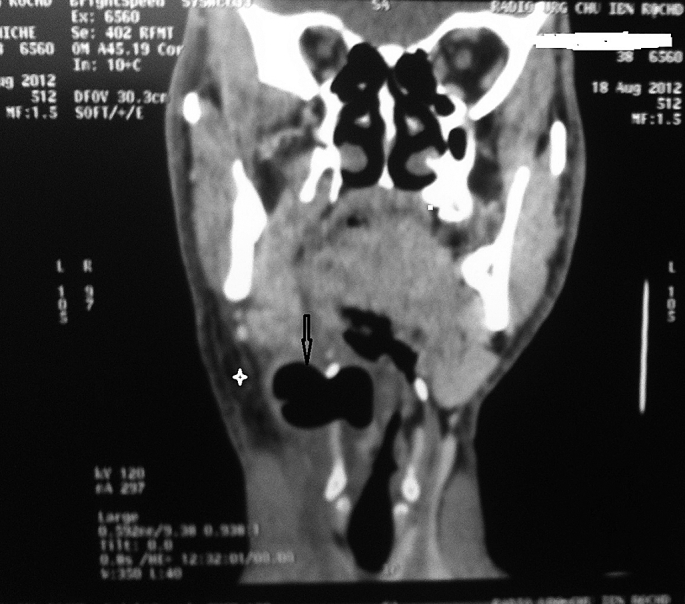

A fine needle aspiration assessment was performed on the neck swelling. This produced air with 15ml of frank pus that was submitted for microscopy, culture and sensitivity testing. High-dose on a course of intravenous Metronidazole and Ceftriaxone were commenced. An urgent CT scan of the neck (Fig. 1, Fig. 2) showed a large right-sided combined pyolaryngocele associated with regional and subcutaneous neck infections. Intravenous antibiotic therapy was continued for one week.

A computed tomography scan revealed a cystic lesion with a hydroaeric level (arrow) in the axial images (Fig. 1) And an intra-extra laryngeal component on the right side with extension through the thyrohyoid membrane of 5 Cm × 3 Cm × 2.5 Cm which could be determined in the coronal sections (Fig. 2), with airway collapse, compatible with a superinfected mixed laryngocoele, associated with emphysema in the deep planes of the neck (asterisk).